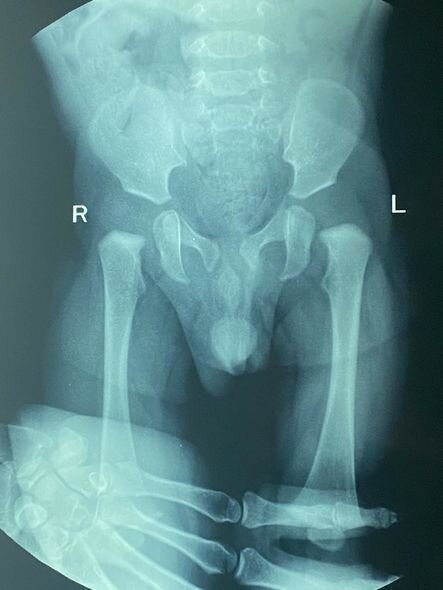

O bildirib ki, övladında anadangəlmə oynaq başcıqları formalaşmayıb.

"Zeyd doqquzaylıqdır. Anadan olanda onda oynaq başcıqlarının formalaşmadığını öyrəndik. İlk gündən də müalicələrə başlamışıq. Hazırda Zeyd xüsusi korset taxır. Müalicələrini bir müddət də davam etdirib, daha sonra əməliyyat olunacaq. Hazırda müalicələr üçün 800 manata ehtiyacımız var".